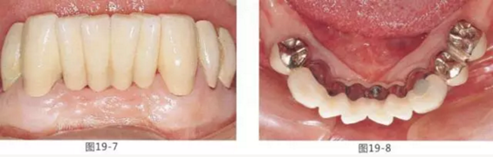

圖19-7 佩戴最終修復5年后的唇頰側面照。

圖19-8 同時期下側咬合面照。